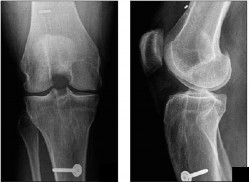

A 16-year-old female undergoes medial patellofemoral ligament (MPFL) reconstruction for recurrent patellar instability. Intraoperative fluoroscopy is used to determine the anatomic femoral attachment site (Schöttle's point). Which of the following radiographic landmarks correctly identifies this location on a strict lateral radiograph?

Options:

- 2 mm anterior to the posterior cortex line, 5 mm distal to the medial epicondyle, and on Blumensaat's line

- 1 mm anterior to the posterior cortex line, 2.5 mm distal to the posterior origin of the medial femoral condyle, and proximal to Blumensaat's line

- 5 mm posterior to the posterior cortex line, exactly on Blumensaat's line

- Directly over the adductor tubercle, 10 mm proximal to the medial epicondyle

- 1 mm posterior to the posterior cortex line, 5 mm proximal to the medial epicondyle, and distal to Blumensaat's line

Correct Answer: 1 mm anterior to the posterior cortex line, 2.5 mm distal to the posterior origin of the medial femoral condyle, and proximal to Blumensaat's line

Explanation:

Schöttle's point is the radiographic landmark for the femoral origin of the MPFL. On a strict lateral radiograph, it is found 1 mm anterior to a line extending from the posterior femoral cortex, 2.5 mm distal to the posterior articular border of the medial femoral condyle, and proximal to the posterior projection of Blumensaat's line.